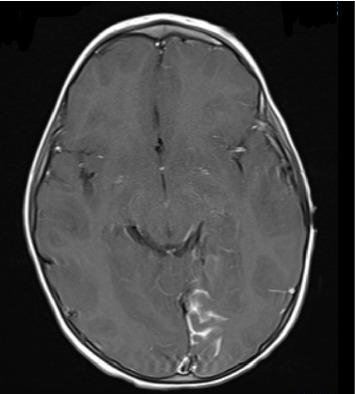

Sturge-Weber Syndrome (SWS), also called encephalotrigeminal angiomatosis, is a rare congenital neurological condition classified by the hallmark findings of a port-wine birthmark, leptomeningeal angiomas, and glaucoma. Here, we present a case of a two-year-old patient with a history of a left-sided port-wine birthmark involving the V1-V2 dermatomes who re-presented to the emergency department with focal right-sided seizure-like activity in the setting of a recent head trauma. The patient was admitted for further workup, where video electroencephalography demonstrated the presence of electrographic seizures developing from the left posterior quadrant, with continuous focal slowing over the left hemisphere, and with magnetic resonance venography revealing findings concerning for a pial angiomatosis. This finding, coupled to new-onset seizure-like activity in a patient with a port-wine birthmark, supported a diagnosis of SWS. He was started on an antiepileptic drug regimen with resolution of seizure-like activity while inpatient and his subsequent care was transferred to a specialized clinic designed to manage patients with SWS. Most patients diagnosed with SWS exhibit seizure-like activity, often presenting as infantile spasms, within the first year of life; our patient, on the other hand, began to exhibit focal seizures following a traumatic event and was later found to harbor findings consistent with SWS. Overall, this case highlights the role of a multidisciplinary team in the management of patients with SWS and demonstrates the importance of routine follow-up testing, imaging, and subspecialty care for these patients.